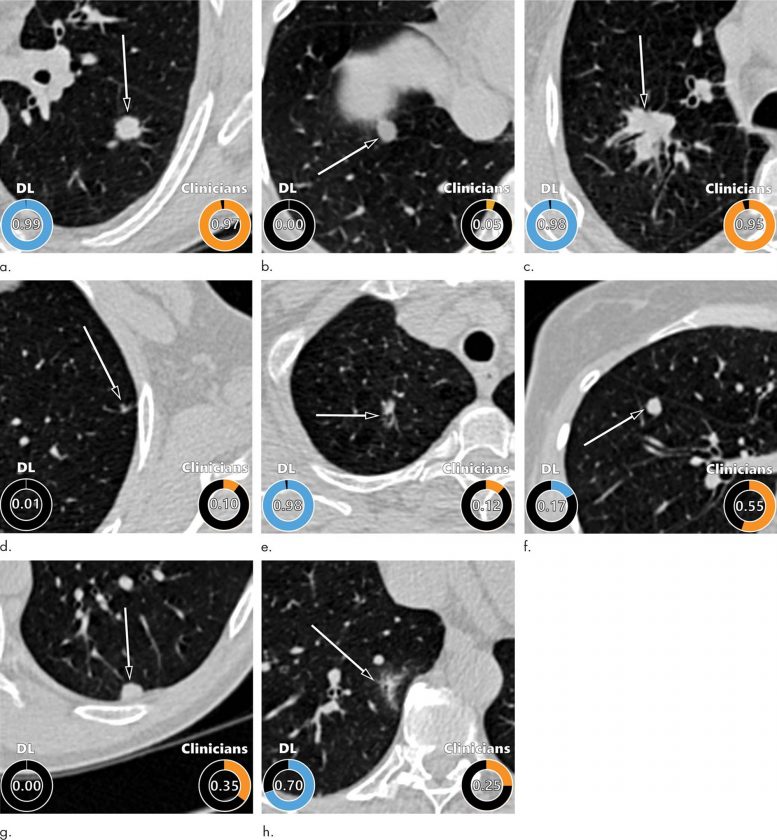

Trong nghiên cứu mới, các nhà khoa học đã phát triển một thuật toán để đánh giá nốt phổi bằng cách sử dụng học sâu, một ứng dụng AI có khả năng tìm thấy các mẫu nhất định trong dữ liệu hình ảnh. Các nhà nghiên cứu đã “đào tạo” cho thuật toán trên hình ảnh CT của hơn 16.000 nốt phổi, bao gồm 1.249 khối u ác tính từ Thử nghiệm sàng lọc phổi quốc gia. Nhóm nghiên cứu đã xác thực thuật toán trên ba bộ dữ liệu hình ảnh lớn về các nốt phổi từ Thử nghiệm sàng lọc ung thư phổi của Đan Mạch.

Thuật toán học sâu đã mang lại kết quả xuất sắc, vượt trội hơn so với mô hình Phát hiện sớm ung thư phổi do Khung Tăng trưởng sạch và Biến đổi khí hậu Pan-Canada thiết lập để ước tính nguy cơ ác tính của các nốt phổi. Thuật toán học sâu đã thực hiện khối lượng công việc tương đương với 11 bác sĩ lâm sàng, bao gồm 4 bác sĩ X quang lồng ngực, 5 bác sỹ X quang và 2 bác sĩ phổi.